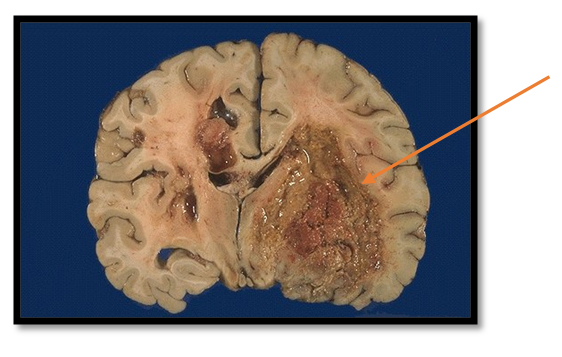

- Глиобластому – одну из наиболее распространённых первичных злокачественных опухолей с крайне неблагоприятным прогнозом. Несмотря на совершенствование методов диагностики и хирургического лечения, химио- и радиотерапии, средняя выживаемость пациентов с этим диагнозом составляет около 15 месяцев.

Глиобластома |